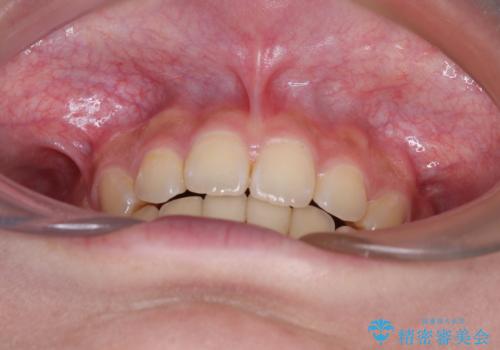

それほど口元の突出感が強いわけではありませんでしたが、下唇に前歯引っかかる感触が気になっていたため、抜歯矯正を行うこととしました。

上下前歯の被蓋が理想通りに改善され、患者様には大変満足していただけました。